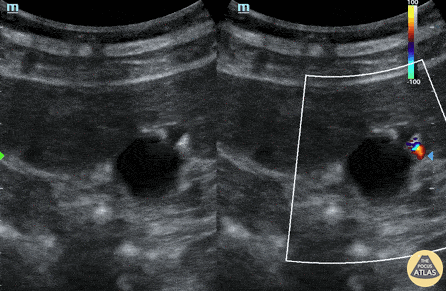

Biliary - Adenomyomatosis

A middle aged patient presented with epigastric pain and vomiting. Ultrasound identified anechoic cystic thickening of the gallbladder wall associated with comet-tail artifact and twinkling artifact. Findings were consistent with adenomyomatosis, a generally benign condition caused by hyperplastic growth of the gallbladder mucosa often associated with chronic inflammation. Michael Cover, MD @michaelc0ver